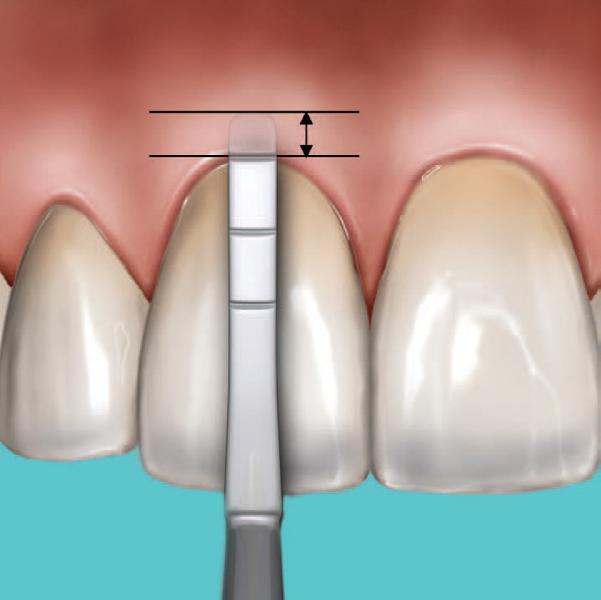

A significant number of people are unhappy with their smile, which has a considerable psychosocial impact. Although many seek cosmetic dental treatment, costs, fear and duration of total treatment are often barriers to the patients. Nevertheless, many could benefit from small and subtle changes to their teeth. With simple direct and freehand techniques, quick but significant results can be obtained that ultimately greatly improve the overall smile aesthetics.

The restoration of abfractions in the anterior area is important for aesthetic appearance especially in patients with high smile lines. Moreover, restoring abfractions strengthens the cervical area of the tooth, prevents further loss of enamel and ameliorates unpleasant sensitivity.

Black triangles and diastemas can cause entrapment of the food and accumulation of bacteria, which leads to gingivitis and ultimately periodontitis. By eliminating the black triangles and diastemas with composite bonding, the dentist not only improves the aesthetics, but also protects the long-term health of the periodontal tissues.

Worn canine cusp restoration is of special functional importance. Creating functional canine guidance with a minimally invasive composite addition to the canine cusp will protect the posterior teeth during lateral movements of the jaw. Incisal wear restorations return the youthful appearance to the smile and prevent further loss of enamel and exposure of the dentinee.